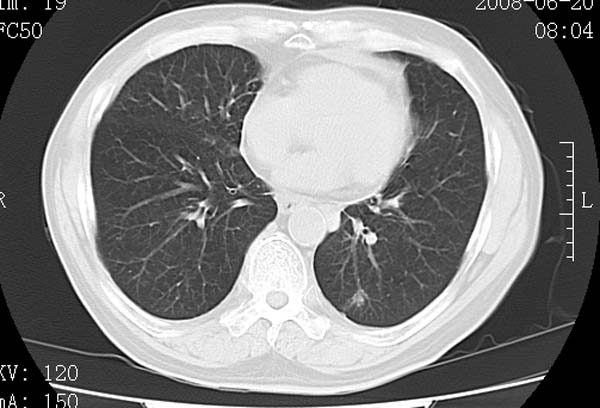

以下是引用守望可可西里在2008-6-24 1:11:00的发言:[br][br] 考虑为周围型肺癌:[br] 1.分叶结节,形态极不规则,蟹足样伸展的恶性浸润特征比较明确。[br] 2.磨玻璃影中由多个更高密度小结节聚集呈梅花瓣样。[br] 3.局部胸膜凹陷征比较明确。[br][br] 另:纵隔胸膜明显增厚、粘连。

以下是引用zjzjr在2008-6-24 11:19:00的发言:[br]支持左下肺周围型肺癌伴右肺转移,纵隔淋巴结转移,心包积液.

以下是引用zhangling在2008-6-24 14:56:00的发言:[br]我们科室意见报告为[br][br]1考虑左下肺周围型肺癌[br]2右肺小结节考虑转移瘤,纵隔淋巴结转移[br]3心包积液. [br] 各位老师分析的相当好 谢意[br]